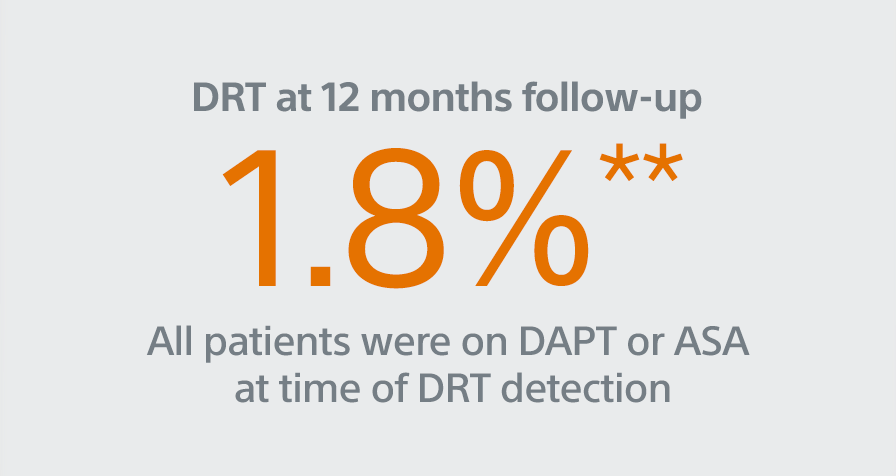

PINNACLE FLX

Study Design

- 400 patient, 29 US site, single arm, non-randomized trial evaluating WATCHMAN FLX for non-inferiority to safety and efficacy performance goals based on the WATCHMAN™ device.

- Follow-up: 45 days (+TEE), 6 months, 12 months (+TEE), 18 months, and 24 months

- Patient Characteristics: Average CHA2DS2-VASc of 4.2±1.5, Average HAS-BLED of 2.0±1.0

- Post Implant Drug Regimen: NOAC/ASA for 45 days, Clopidogrel/ASA to 6 months, ASA post 6 months

- Primary Safety Endpoint: All-cause death, ischemic stroke, systemic embolism, or device- or procedure-related adverse events requiring surgery or major endovascular intervention within 7 days following the procedure or by hospital discharge, whichever is later.

- Primary Efficacy Endpoint: The rate of effective LAA closure defined as any peri-device flow ≤5mm demonstrated by TEE at 12 months

- Secondary Efficacy Endpoint: The occurrence of ischemic stroke or systemic embolism at 24 months from the time of enrollment

- Inclusion/exclusion criteria is consistent with WATCHMAN clinical study inclusion/exclusion criteria. Patients must be eligible for short-term NOAC vs warfarin in previous clinical studies.